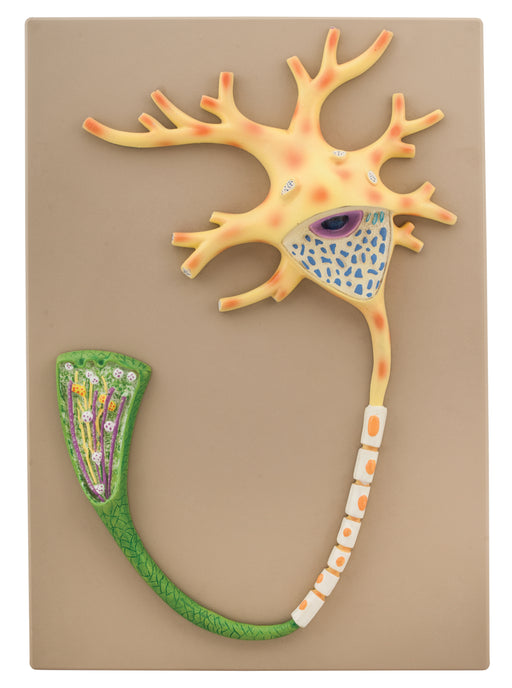

Neuron

Magnified more than 2500 times and fully three-dimensional, a neuron model is depicted in its natural setting. With the membranous envelope cut awa...

View full detailsAM16054 -

Neuron L.S.

This model showing neuron end and structure of nerve fiber. Mounted on base. Supplied with English Key Card. Size 42 x 30 x 7 cm approx. Weight 855...

View full detailsAM16053 -